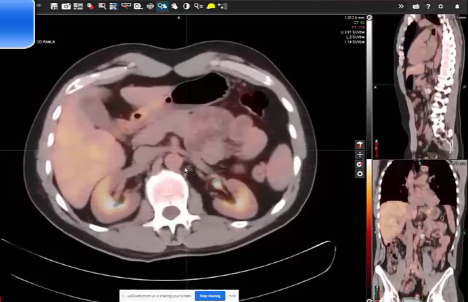

Follicular lymphoma, R-CHOP Chemotherapy, DLBCL, nodular lymphoma, post treatment scans, testicular lymphoma, photons vs. electrons, target volumes, dose, side effects, paranasal lymphoma, elderly, multiple myeloma, bone mets,

nodular sclerosis, Hodgkin's lymphoma, supraclavicular lymph nodes, MALT lymphoma, CLL,